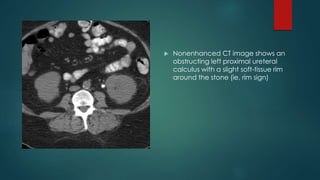

 Nonenhanced CT image shows an

obstructing left proximal ureteral

calculus with a slight soft-tissue rim

around the stone (ie, rim sign)